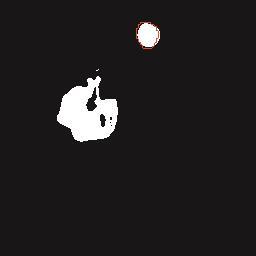

基于逐通道空间自适应选择核卷积与双向边界感知机制的乳腺超声图像病变分割网络

A Breast Ultrasound Images Lesion Segmentation Network Based on Channel-Wise Spatially Adaptive Selective Kernel Convolution and Bidirectional Boundary-Aware Mechanism

乳腺癌是全球女性最常见的恶性肿瘤之一,准确的病变分割对于乳腺癌的早期诊断与治疗具有重要意义。然而,由于病变形态的多样性以及超声成像机制的复杂性,现有基于深度学习的乳腺超声图像病变分割方法在分割准确性方面仍面临巨大挑战。为进一步提升乳腺超声图像中病变区域的分割精度,该文基于经典U-Net架构,提出了一种新型乳腺超声图像病变分割网络(CWSASKM-BBAM-Net)。首先,在网络中引入逐通道空间自适应选择核卷积模块(CWSASKM),根据不同通道的语义特征为每个空间位置自适应选择感受野大小,以增强多尺度信息的建模能力;然后,引入双向边界感知机制(BBAM),通过融合正向与反向注意力,对目标显著区域及其边界进行协同建模,同时逐步提升对非显著区域与病变区域的区分能力,以进一步强化边界信息的表达;最后,在3组公开乳腺超声图像数据集(BUSI、UDIAT和STU)上开展分割实验。结果表明:该方法在数据集BUSI上的杰卡德指数、精确率、召回率和Dice相似系数分别为71.97%、82.85%、81.40%和80.44%,较次优方法分别提升1.69、1.05、1.28和1.84个百分点;在数据集UDIAT上,这4项指标分别达到78.14%、88.31%、86.73%和86.10%,较次优方法分别提升了2.75、2.04、0.56和2.01个百分点;在外部数据集STU上,该方法也取得了优于其他方法的整体表现。实验结果表明,CWSASKM-BBAM-Net在乳腺超声图像分割任务中展现出更优的整体性能。